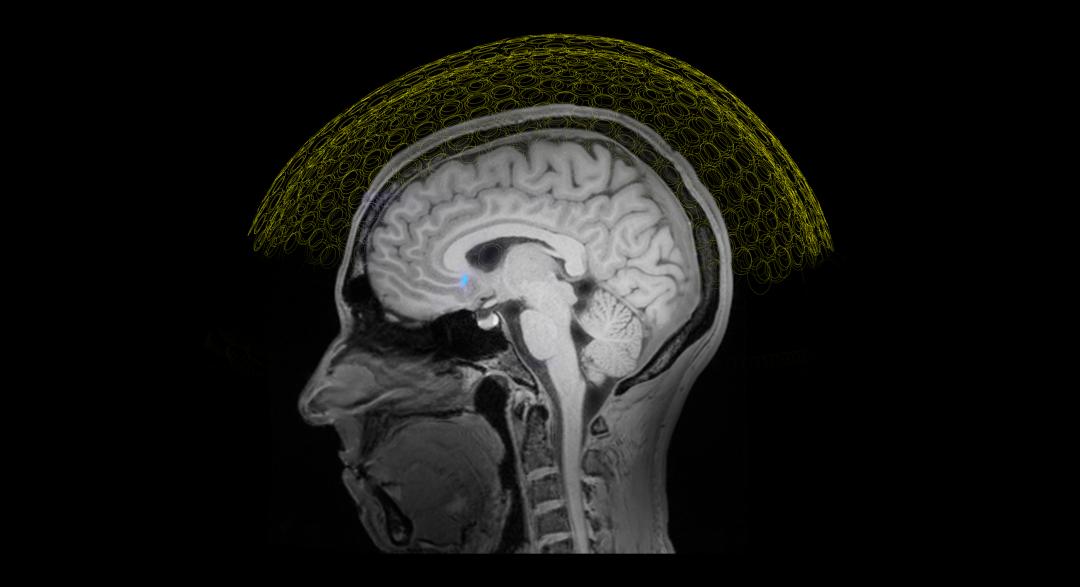

超声用于脑机接口,好处第一就是它的成像的范围可以放大到全脑,我们做过测算,比方说以Neuralink同等大小的这么一个设备,作为一个探头的话,放在这个位置,也就是从电学脑机接口换成超声脑机接口,它对脑区的覆盖范围是什么区别?Neuralink是插进去整个大脑皮层的1.3‰,而超声脑机接口放在同样的位置可以对整个大脑体积的25%成像。

图片来源:sanmai.tech

泓君:什么设备,戴在什么位置?

彭雷:一个头盔,超声脑机接口的一个探头,放在大脑颅骨位置。假设跟Neuralink一样的位置。Neuralink把这里的头皮掀开,把骨头拿走,放一个硬币大小的设备在这里,对吧?那假设我们把超声也做到这么小了,放在同样的位置,我能监控的大脑区域的体积是25%,这是个空间上的区别。

时间上,现在我们还做不到像电学那么高的时效性,但这个时效性也可以比fMRI(功能核磁成像)要好很多了。功能核磁这个信号延迟,可能大几秒钟,甚至10秒钟都有可能。但是超声可以把血流信号的成像时间,基本上做到1.5秒,或者是0.5秒。而且能看到的血流信号本身其实在超声下是没有什么延迟的,基本上是实时的。

彭雷:这里面有个非常重要的逻辑,就是颅骨。超声波在大脑内,不管是“读”还是“写”,最大的一个障碍就是骨头,没有之一。骨头会让超声波出现散射,而且这种散射是不规律的,因为每个人的颅骨的厚度、颅骨里面的空腔大小,都不太一样,从算法的角度来讲非常复杂。所以做调控的时候,隔着颅骨打进去,就做不到特别精巧的聚焦。去掉颅骨之后,大脑在超声面前基本上就是透明的。大脑本身也是包在脑脊液里面的,而脑组织神经元,跟脑脊液,跟硬膜,在超声传递的过程中都不会形成散射,不会有重大的信号的偏离。